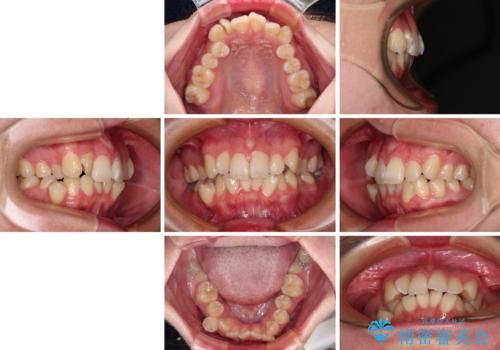

- 上下前歯のデコボコを気にして来院された患者様です。

口元の突出感はあまりなかったものの、デコボコを非抜歯で改善すると出っ歯になる可能性があるため、上下左右の第一小臼歯4本を抜歯し、ワイヤー装置にて矯正治療を行うこととしました。